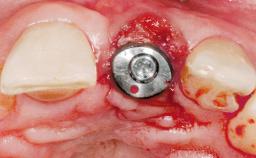

Immediate Placement of an Implant in a Maxillary Left Central Incisor Site

A 33-year-old female patient presented with an upper left central incisor that required extraction after a failed endodontic therapy. The tooth had been traumatized when the patient was a teenager and had undergone several endodontic treatments, including two apicectomy procedures. The patient was in good health and did not smoke. Clinical examination showed that the patient had a high lip line. In full smile, the gingival margins of the upper teeth were visible to the first molars. The gingival margins of central incisors 11 and 21 were only just showing. Examination of tooth 21 confirmed that the tooth was mobile and had hypererupted by 1 mm.